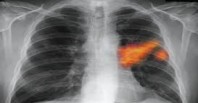

საკვერცხეების სიმსივნე - მომაკვდინებელი დაავადება, რომელსაც თანამედროვე მსოფლიოში სულ უფრო და უფრო ხშირად ვხვდებით. რა თქმა უნდა, ნებისმიერი სახის სიმსივნის განკურნება შესაძლებელია, თუ პრობლემას დროულად აღმოვაჩენთ და მივმართავთ სპეციალისტს დახმარებისთვის. საკვერცხეების სიმსივნე, სამწუხაროდ, საწყის სტადიაზე შეუმჩნევლად მიმდინარებს და მისთვის მხოლოდ ზოგადი სიმპტომებია დამახასიათებელი, რის გამოც ამ დაავადებას ხშირად ''ჩუმ მკვლელად'' მოიხსენიებენ.

ხშირად ქალბატონების უმრავლესობა ამ საშინელი დაავადებისთვის დამახასიათებელ სიმპტომებს ჯანმრთელობასთან დაკავშირებულ სხვა პრობლემებს მიაწერს, რაც 95% შემთხვევაში სავალალოდ სრულდება.

საკვერცხეების სიმსივნის განსხვავება სხვა დაავადებისგან შესაძლებელია კონკრეტული გამოვლინებების მიხედვით. სამწუხაროდ, ქალბატონების უმრავლესობა ამ ინფორმაციას არც ფლობს, რაც უპატიებელი შეცდომაა.